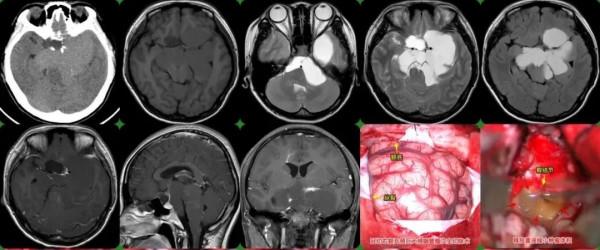

入院後,我院院長張永力、神經外科二病區副主任楊海洋查體、完善檢查及閱片後,考慮顱咽管瘤可能,右眼視力下降明顯,5cm內視物均模糊,有明顯手術指徵,需手術治療。

腫瘤巨大,橋前池、橋小腦角池、鞍上池、環池佔位性病變,橋腦、中腦、四腦室受壓變形,要透過各個狹窄的手術間隙分塊將腫瘤切除,還要保護周圍的重要神經血管,手術難度較大。

經過術前評估,詳細制定手術方案,並於家屬溝通,張院長及楊主任帶領團隊為其實施了全麻下“冠切右額開顱前縱裂入路巨大顱咽管瘤切除術”。

術中可見腦組織較腫脹,腫瘤大量鈣化,多個瘤囊,和左側視神經、視束、視交叉粘連緊密,外側和頻內動脈及大腦中動脈、大腦前動脈、後交通動脈粘連緊密,並部分包裹,經過不懈努力,神經和血管儲存完好,手術順利,術後患者恢復良好。

術後病理診斷確診為顱咽管瘤。